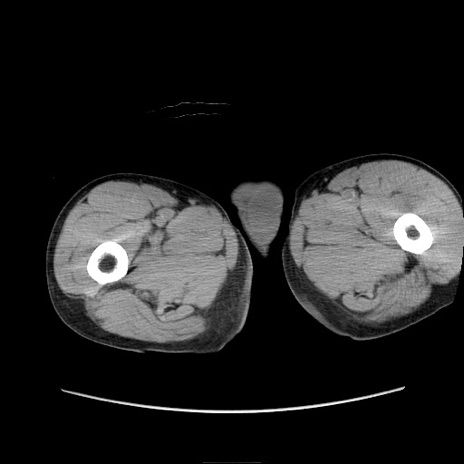

症例11(横断像)

【症例】 60歳代男性

【主訴】 下腹部痛

【現病歴】 本日夜中より下腹部痛の症状認め、受診。

【既往歴】 膀胱癌(膀胱全摘+尿管皮膚瘻術) 、胃癌術後

【身体所見】 BT 35.3℃、PR 58/min、BP 136/98mHg、腹部平坦、軟、腸蠕動音±、ストマ留置あり、左上腹部~正中部に圧痛あり、反跳痛なし。

【データ】WBC 5100、CRP0.01